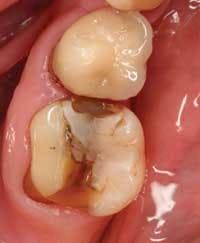

It truly is an exciting time to practice dentistry. There are so many advances that have impacted our collective dental practices that the art of dentistry has now blended with modern technology to provide an enjoyable dental experience for both clinician and patient. A dental visit can now be comfortable, efficient, and practical, in that a patient’s broken tooth can be permanently restored to optimal form, function, and esthetics in a single visit with a simple procedure (Figure 1).